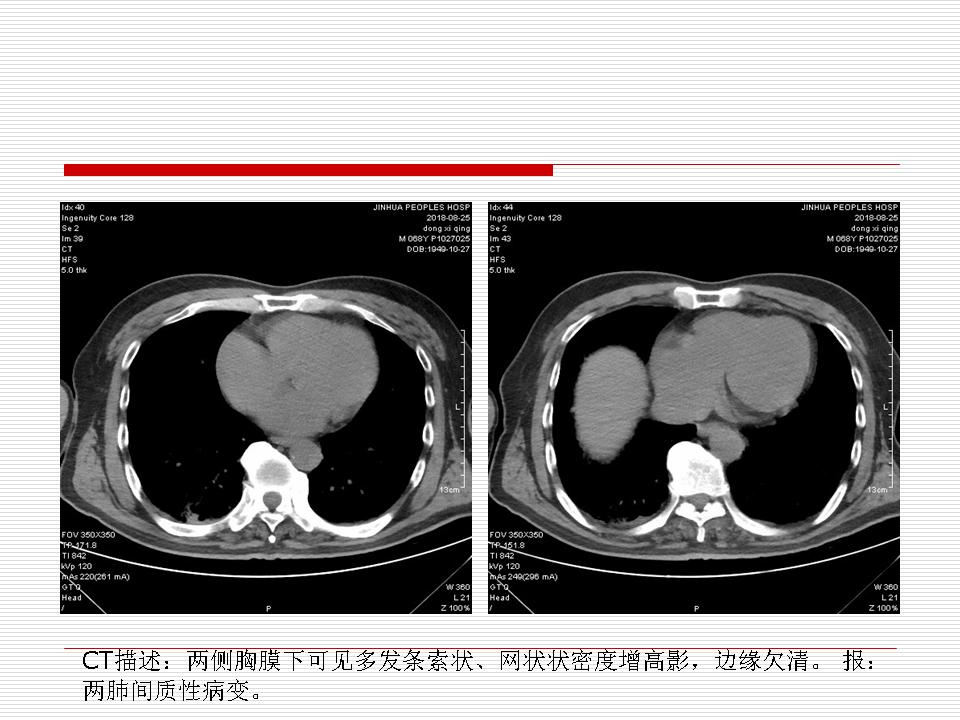

肺部阴影永恒且最重需要鉴别的是:到底是炎症还是肿瘤?但临床的病例中的影像表现难以界定或有些肿瘤特征,同时又有些炎症特点是非常常见的情况。作为临床医生我们怎么去总结分析,并找到之所以是炎症或之所以是肿瘤的细微差别或特点非常重要,也非常有用。2019.12.7浙江省2019年胸心外科学学术年会在宁波召开时,我的临床病例分析与经验总结<那些像肺癌的炎症与像炎症的肺癌>获得在大会交流的机会,以下为该PPT的内容,与你分享,希望对同道有益,有借鉴与启迪。若有探讨与进一不完善的建议,欢迎文末留言讨论: